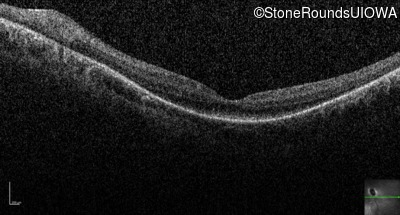

Optical Coherence Tomography - Right - 20/100 +1

Exemplar / OCT Stack